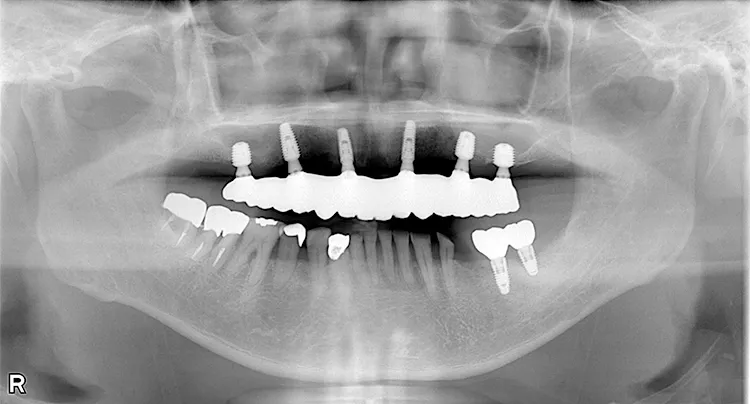

症例8/

下顎ボーンアンカードブリッジ

- 治療期間

- 6ヶ月

- 費用

- 265万円(税込)

治療前

治療後

レントゲン画像

治療内容

ボーンアンカードブリッジの下顎症例です。同じようにインプラント6本で上部構造を支えることができます。